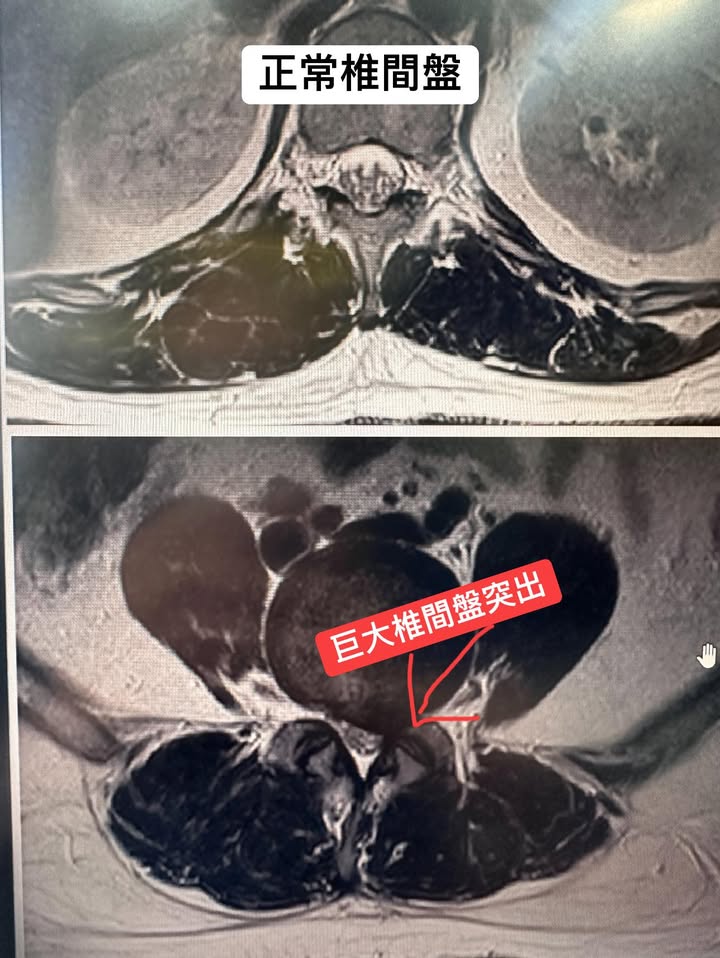

⭐️這就真的是巨大椎間盤突出脫垂案例